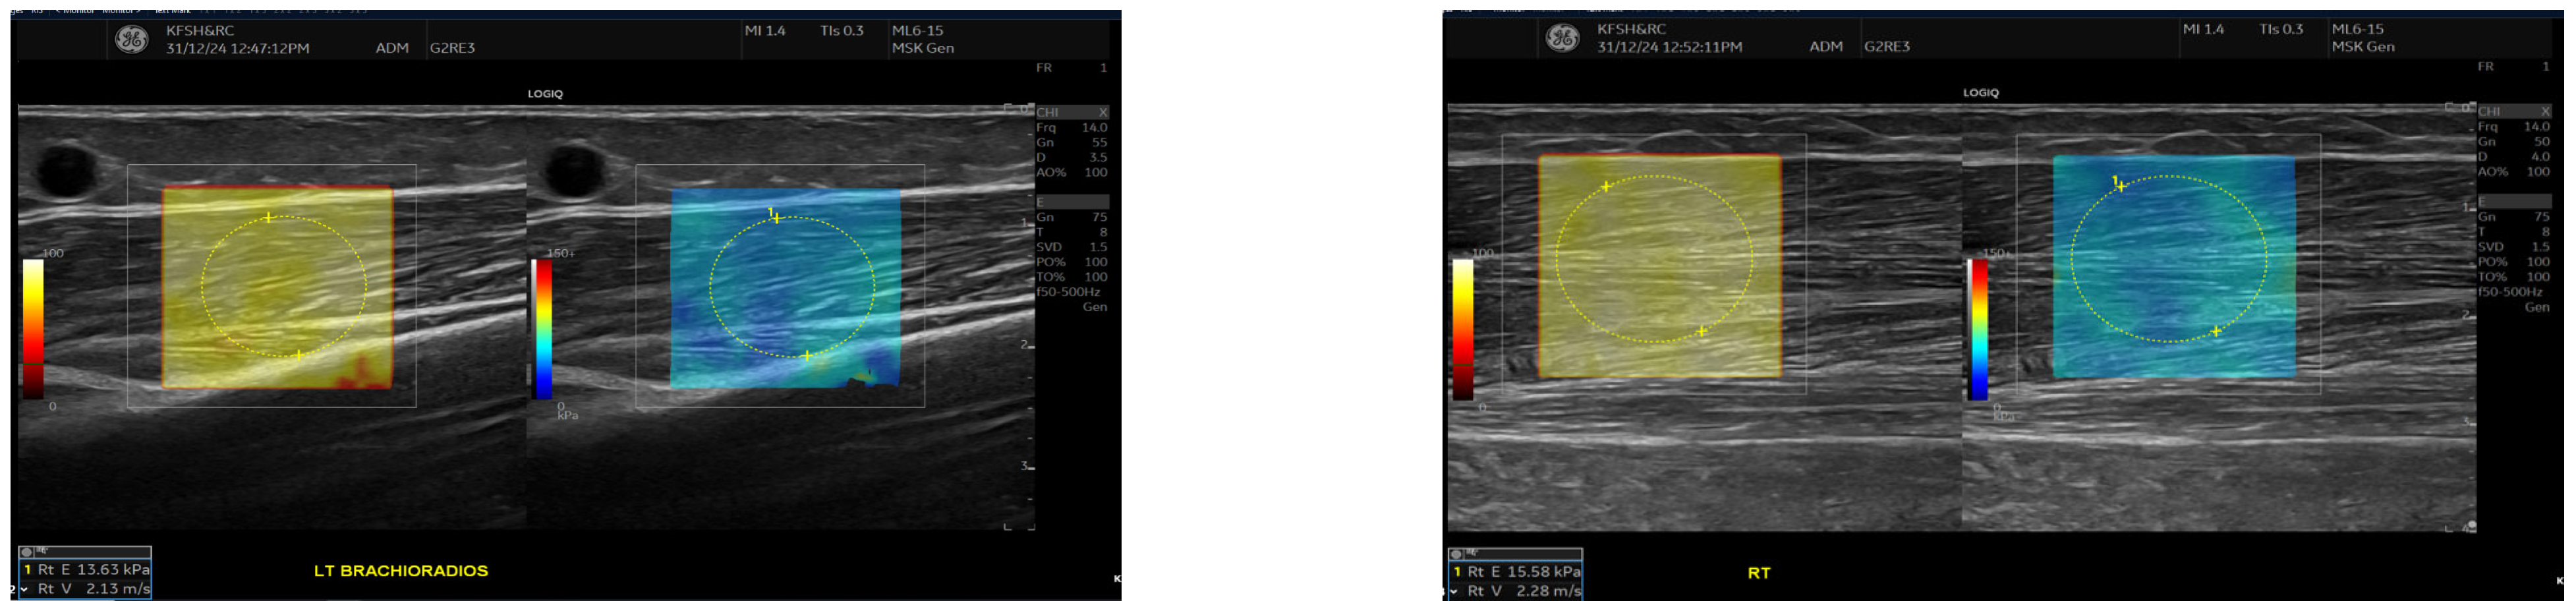

SWE measurements were acquired using a GE LOGIQ E10 (GE HealthCare, Chicago, IL, USA) system equipped with an ML 6-15 D linear transducer (frequency 6–15 MHz). Depth settings were standardized at 2.5–3.5 cm depending on muscle thickness. Each ROI was circular with a 5–7 mm diameter, placed centrally within the elastograms, avoiding fascia, vascular structures, and visible artefacts. Stiffness values were recorded in both kilopascals and metres/second, although statistical analyses were conducted using shear-wave velocity (m/s) for consistency. Frames with motion or colour dropout were discarded and reacquired. Muscle stiffness and thickness were evaluated in the biceps brachii and brachioradialis muscles, located proximal to the AVF site, Figure 1 and Figure 2. SWE imaging provided both Colour-coded elastograms and quantitative stiffness measurements (m/s; Figure 3). Participants were examined supine, with the shoulder in neutral rotation, the elbow extended to approximately 10–20°, and the forearm supinated. This minimized passive tension, which can influence shear-wave velocity. The transducer was positioned perpendicular to the muscle fibres, capturing measurements from the proximal, middle, and distal regions for comprehensive analysis. Measurements were taken before the haemodialysis to avoid intravascular volume shifts, with each parameter recorded three times and averaged for precision. Scans were performed by an experienced sonographer and verified by a radiologist, minimizing bias. A preliminary review of some patient records was conducted to refine data collection tools before the main data collection.

Figure 1.

This figure shows the Ultrasound assessment of stiffness near the arteriovenous fistula site (A) and brachioradialis muscle thickness (B). Shear wave elastography images (A) obtained at the fistula side demonstrate quantitative stiffness mapping within a defined region of interest, with stiffness expressed in velocity in metres per second (m/s). B-mode image (B) showing brachioradialis muscle thickness measurement at the contralateral (right) arm.

Figure 3.

This figure shows the comparison of brachioradialis muscle stiffness between the fistula and the contralateral arm. Shear wave elastography images showing stiffness measurements of the brachioradialis muscle. The left panel (fistula side) demonstrates a mean elasticity (velocity 2.13 m/s), while the contralateral arm (right panel) shows slightly higher stiffness (velocity 2.28 m/s). Measurements were taken in the mid-muscle belly using a high-frequency linear transducer, with Colour maps indicating relative stiffness (warmer colours represent higher stiffness).